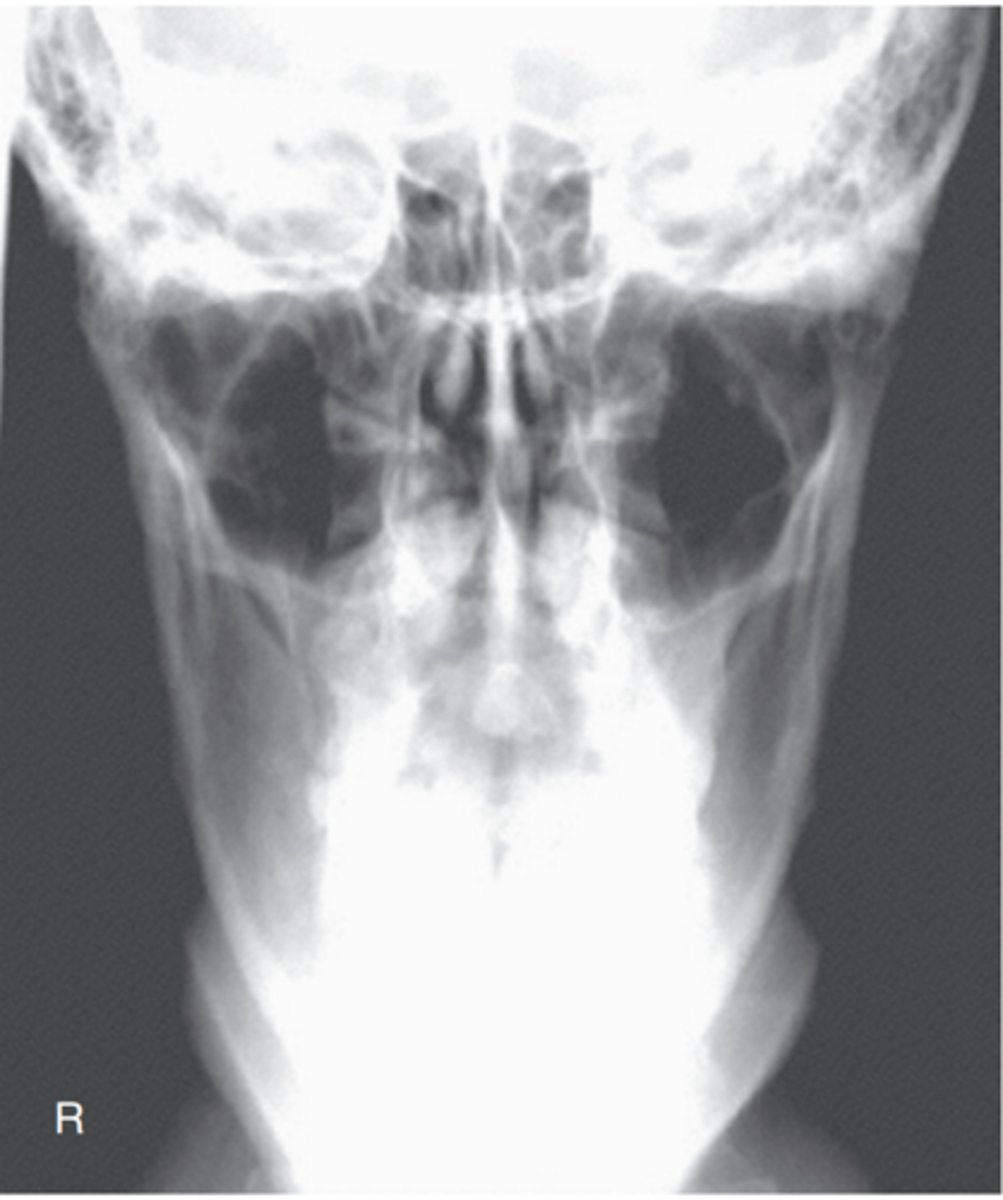

Is this a PA or AP projection? are there any errors?

-This is an AP 15° cephalad projection, as evidenced by the large size of the orbits resulting from magnification caused by increased OID

Repeatable errors (three)—

Criterion 2: Positioning

Criterion 3: Collimation and CR: The petrous ridges are not projected into the lower one-third of orbits. More flexion of neck or less CR angulation is required. The skull also is slightly rotated (note distance between orbits and lateral margins of skull) and tilted.

Criterion 5: Anatomic side markers: Anatomic side marker is missing.